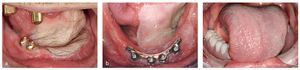

No pocas veces, el prostodoncista ve a los pacientes que se interesan por una posible rehabilitación intraoral en el estado tras la conclusión del tratamiento inicial (fig. 1a). El puenteo del defecto mediante trasplantes óseos y colgajo miocutáneo, realizado simultáneamente a la operación del tumor, con frecuencia termina en la ausencia de cualquier piel fijada en el sentido de una mucosa de la cresta alveolar, así como de un vestíbulo. Generalmente, en esta situación todavía se encuentran in situ las placas de fijación con las cuales se ha fijado el hueso sustitutivo al maxilar inferior remanente. En este punto, a menudo todavía no se ha proporcionado una solución para la lengua, en caso de que aquélla sea factible. Paralelamente existen además las consecuencias de la irradiación, en este caso apreciables claramente en la sequedad de la boca y las lesiones cariosas en los dientes. En una situación así no es posible planificar los implantes con montajes simulados. De ahí que sea preciso considerar compromisos en cuanto a la posición del implante. En casos con dentición antagonista presente pero apertura máxima de la boca limitada, es imprescindible tratar también el maxilar opuesto.

Junto a los problemas del vestíbulo aún ausente y a la movilidad deficiente de la lengua que con seguridad ya no se podrá restablecer mediante solución, en este caso se debe considerar también el cierre incompetente de los labios (fig. 1b). Durante la primera sesión, el prostodoncista tiene la tarea de informar al paciente de que la colocación de una reposición dental no conducirá en ningún caso a un resultado funcional totalmente satisfactorio. Sin embargo, la reposición mejorará probablemente la situación psicosocial.

Sólo tras la puesta al descubierto se puede formar el vestíbulo mediante un injerto (fig. 1c). Durante la operación de puesta al descubierto se coloca al paciente una placa de vendaje que no puede retirar durante aproximadamente los primeros diez días. A continuación, el prostodoncista confecciona una placa removible que se retiene en las supraestructuras de cicatrización o mediante telescópicas, si bien esto último es más costoso. El paciente debe llevar siempre esta placa, a fin de mantener el injerto en su sitio y para evitar que el vestíbulo recién creado se contraiga. A partir de ahora es preciso limpiar cuidadosamente los implantes. El resto del tratamiento protésico no debería tener lugar demasiado pronto, a fin de no arrancar de nuevo el injerto durante la retirada de la toma de impresión de precisión de los implantes.

La técnica de cubeta abierta por arriba es la impresión más precisa en caso de implantes múltiples (fig. 1d). En el modelo de estudio, en el que en estos casos deben ser siempre reconocibles para el protésico los implantes y su inclinación axial aproximada, se confecciona alrededor de los implantes una cubeta abierta por arriba con espacio suficiente para el material de impresión. En caso de que la cubeta en la boca roce con uno de los postes de impresión, será preciso tallarla. En consecuencia, las paredes de la cubeta no deben ser excesivamente delgadas. Con arreglo a la función, se forma mediante material termoplástico la parte dorsal. Antes de tomar la impresión, se cierra con cera de modelado la abertura sobre el poste de impresión, se repone la cubeta y se presiona la cera hasta las cabezas de tornillo de los postes de impresión. Esto facilita posteriormente la localización de los postes de impresión.

En caso de que la apertura máxima de la boca o la dentición antagonista no admita la longitud completa de los postes de impresión, es posible acortarlos individualmente (fig. 1e). Sin embargo, es preciso tallar un número suficiente de zonas retentivas, para que los postes no se salgan inadvertidamente del material de impresión al retirar la impresión.

Antes de confeccionar una mesoestructura sobre los implantes, debe tener lugar obligatoriamente una prueba en cera tras una determinación de la relación maxilar y una transferencia con arco facial (fig. 1f). Es posible facilitarle al protésico la confección de las plantillas si ya durante la toma de impresión se ha tomado una relación provisional mediante una masilla de silicona sencilla, dado que la relación posicional entre los maxilares superior e inferior rara vez es normal. Preferentemente, se aplica la silicona como soporte sobre una horquilla de mordida de un arco facial, el cual puede ya crearse en esta sesión. Como plantilla de mordida en el maxilar superior está indicada una llave de resina, a fin de llevar a cabo con ella nuevamente al mismo tiempo una transferencia con arco facial más precisa. En cambio, en el maxilar inferior se utiliza una llave realizada en una cera dura de toma de mordida. A fin de definir el asiento, se ancla esta plantilla a los implantes mediante postes de impresión acortados. A este respecto debe tenerse en cuenta, desde el punto de vista protésico, que el odontólogo pueda observar desde vestibular si los postes de impresión están correctamente posicionados en el implante. A menudo es preciso llevar a cabo, tanto en el maxilar superior como en el inferior, correcciones para la configuración de las partes blandas. Esto puede tener lugar mediante reducción de las plantillas o aplicando cera de modelado. Si el prostodoncista ha logrado en el paciente un apoyo adecuado del perfil de los labios, el protésico puede adoptar la situación mediante una llave de silicona. En tales casos tampoco deberían faltar las líneas auxiliares, dado que también aquí pueden haberse creado diferencias considerables con respecto a una situación normal debido a los tratamientos previos. En caso de tumores extendidos en el maxilar inferior, con no poca frecuencia resulta una relación intermaxilar fuertemente alterada (fig. 1g). Debido a la apertura máxima limitada de la boca, al cierre incompetente de los labios y a la movilidad deficiente de la lengua, en este caso debe ajustarse una altura de mordida baja. La relación posicional con espacio disponible reducido debido a las retracciones cicatriciales, ya de por sí alterada por la operación, se ve dificultada adicionalmente para el protésico dental por el establecimiento de una vertical baja.

Fig. 1a. Ésta es una situación típica al concluir el tratamiento en caso de malignomas extendidos. b Llama la atención aquí la piel que ha adquirido una apariencia como de cuero debido a la radioterapia, así como la ausencia de crecimiento de barba en la zona de irradiación. c Las placas de vendaje para mantener la vestibuloplastia alcanzada pueden confeccionarse en resina protésica transparente. d Siempre que sea posible, debería tomarse la impresión de los implantes siempre utilizando la técnica de cubeta abierta por arriba. e La individualización de los postes de impresión debería tener lugar ya en la técnica. f Gracias a la entalladura bucal en la plantilla de mordida inferior se tiene la posibilidad de observar si la plantilla también está bien anclada en el implante. g Los desplazamientos intermaxilares tridimensionales no son infrecuentes tras la extirpación de un tumor extendido. h El paciente enseña demasiado los dientes inferiores y ya no puede cerrar los labios. En consecuencia, es preciso corregir el montaje en cera. i Pese al escaso espacio disponible, la barra posee la altura suficiente para retener correctamente la prótesis dental. En casos de apertura reducida de la boca y escasa movilidad de la lengua, es preferible prescindir de cerrojos y utilizar en su lugar espigas de fricción. j Con frecuencia, en caso de escasez del espacio disponible sólo se pueden montar dientes hasta los premolares. k Pese a las condiciones difíciles se ha alcanzado un resultado por lo menos estéticamente satisfactorio (prótesis: protésico dental Rolf Bachmann).

El primer montaje en cera muestra claramente que el cierre incompetente de los labios será uno de los principales problemas de esta restauración (fig. 1h). Pese a que el protésico dental ya ha situado a partir de la relación maxilar el frente inferior muy hacia dentro, pero aun así lo suficientemente por anterior como para permitirse un cierto margen de maniobra para la confección de una barra fresada con racor, los dientes se encuentran todavía demasiado hacia anterior. En casos limitados de esta manera, es preferible evitar las medias tintas y esperar hasta que se haya alcanzado una prueba de cera en boca que represente el resultado funcional estético en la situación individual. Sólo con la ayuda de la prueba de cera en boca optimizada, el protésico dental puede alcanzar el posicionamiento óptimo de la mesoestructura. Por una parte, debe tener cuidado de no perturbar con la construcción las partes blandas comprometidas, y por otra parte debería aprovechar de forma óptima en altura y en la sagital el espacio para una estabilización suficiente de la prótesis dental removible. En este caso se pone de manifiesto que el implante distal en el lado izquierdo no puede hacerse aprovechable, precisamente debido a la insuficiencia de espacio vertical (fig. 1i). Se utiliza exclusivamente para el apoyo, pero no para la retención de la prótesis dental. En caso de una abertura de la boca considerablemente estrechada, deberá renunciarse a un cerrojo. Debido al cierre de los labios comprometido, debería renunciarse a cualquier base también en el maxilar superior (fig. 1j). Al observar detenidamente la reducida separación de los dientes en el frente inferior, así como el opáquer prácticamente translúcido y el racor metálico, es fácil adivinar que el protésico dental debe manejar el espacio de forma óptima en tales casos.

La situación final desde delante muestra que el paciente continuará teniendo previsiblemente problemas con el cierre de los labios (fig. 1k).